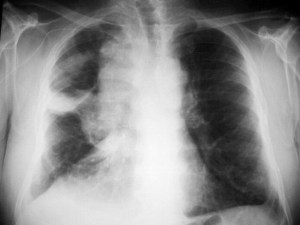

SIGNO DEL CASQUETE APICAL IZQUIERDO

La aparición de una densidad en el ápex pulmonar izquierdo, de borde inferior cóncavo y bien delimitado (casquete apical) en un paciente con traumatismo torácico, debe hacernos sospechar la existencia de una rotura aórtica.

Deben excluirse otras causas de casquete apical, especialmente las lesiones residuales tuberculosas, que suelen acompañarse de otros hallazgos como tractos fibrosos pleuro-parenquimatosos, pérdida de volumen en el lóbulo superior, granulomas, etc.

Mostramos un caso de rotura aórtica por accidente de moto. En este paciente también aparece el signo de la alteración del contorno aórtico.